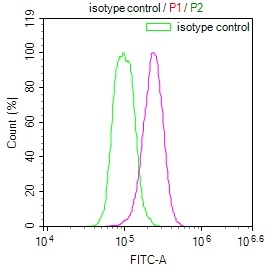

The image on the left is immunohistochemistry of paraffin-embedded Human gastic cancer tissue using CSB-PA051152(CYP2D6 Antibody) at dilution 1/30, on the right is treated with synthetic peptide. (Original magnification: ×200)